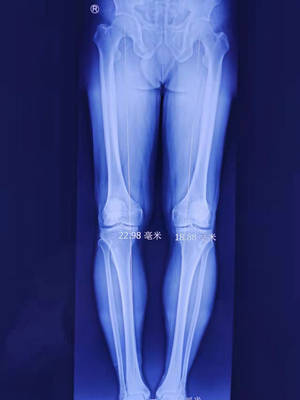

關節科邱東新醫生檢視X光片,發現其為雙側膝關節炎,又結合張師傅行走步態,發現他膝關節已經出現內翻畸形。鑑於張師傅才50歲,為保障他以後的生活,建議他應該首選保膝手術,為了不影響日常生活,手術團隊討論後決定先為其左膝採用關節鏡探查、機器人精準定位脛骨截骨術。

邱醫生告訴張師傅,雖說是截骨,但不會真正的把骨頭截斷,也不會移除任何骨頭。而是在膝關節內側,在小腿骨或大腿的合適位置截開一個穩定的骨面,再把截骨面以合適的角度撐開,並用接骨板固定,以矯正下肢力學軸線。而矯正力線後,行走時以往過度磨損側的壓力會減低,疼痛自然就緩解了。而且術後一兩天就可以下地,以後也不影響任何正常生活。